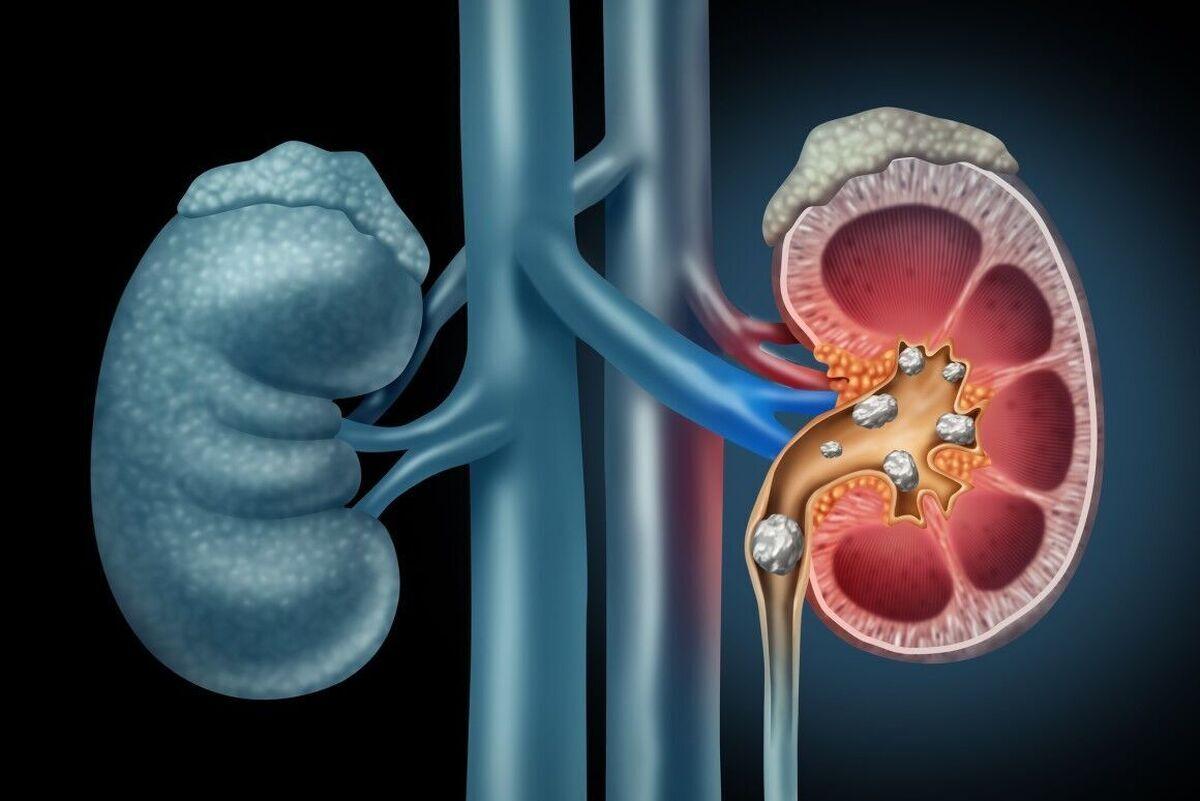

302 - این کارها باعث ایجاد سنگ کلیه می شود

اینتیتر- پزشکی- 16 ماه پیش - شنبه 16 دی 1402، 12:18 70809695

اینتیتر- پزشکی- 16 ماه پیش - شنبه 16 دی 1402، 12:18 70809695

سنگ های کلیه رسوباتی سخت از جنس مواد معدنی (کلسیم، اگزالات و فسفات) هستند که در کلیه های شما تشکیل می شوند. ابتلا به سنگ کلیه دلایل زیادی دارد و می تواند هر بخشی از دستگاه ادراری شما از ...

303 - این کارها باعث ایجاد سنگ کلیه می شود

صد آنلاین- پزشکی- 16 ماه پیش - شنبه 16 دی 1402، 09:53 70806872

صد آنلاین- پزشکی- 16 ماه پیش - شنبه 16 دی 1402، 09:53 70806872

صد آنلاین | سنگ های کلیه رسوباتی سخت از جنس مواد معدنی (کلسیم، اگزالات و فسفات) هستند که در کلیه های شما تشکیل می شوند. ابتلا به سنگ کلیه دلایل زیادی دارد و می تواند هر بخشی از دستگاه ...

305 - این عادت های غلط سنگ کلیه می سازند

آفتاب- پزشکی- 16 ماه پیش - چهارشنبه 13 دی 1402، 20:40 70781791

آفتاب- پزشکی- 16 ماه پیش - چهارشنبه 13 دی 1402، 20:40 70781791

سنگ های کلیه رسوباتی سخت از جنس مواد معدنی (کلسیم، اگزالات و فسفات) هستند که در کلیه های شما تشکیل می شوند. ابتلا به سنگ کلیه دلایل زیادی دارد و می تواند هر بخشی از دستگاه ادراری شما از ...

310 - سنگ کلیه دارید ؟ این گیاهان مخصوص شماست

صد آنلاین- پزشکی- 16 ماه پیش - شنبه 25 آذر 1402، 09:08 70538584

صد آنلاین- پزشکی- 16 ماه پیش - شنبه 25 آذر 1402، 09:08 70538584

صد آنلاین | سنگ کلیه، تشکیل سنگ در کلیه، یکی از قدیمی ترین و شناخته شده ترین بیماریها در دستگاه ادراری با میزان عود 50 درصد50در بازه زمانی 5 تا 10 سال است. - به گزارش صد آنلاین ، سنگ کلیه ...

320 - چرا سنگ کلیه می گیریم؟ / بهترین نوشیدنی برای پیشگیری از بیماری های کلیوی

ریمینو- پزشکی- 17 ماه پیش - یکشنبه 19 آذر 1402، 10:19 70466018

ریمینو- پزشکی- 17 ماه پیش - یکشنبه 19 آذر 1402، 10:19 70466018

منبع ریمینو مشکلات در زندگی ماشینی، پشت میز نشستن و نداشتن حرکت کافی منجر به پیدایش بسیاری از بیماری ها به ویژه سنگ کلیه شده است. اگرچه این بیماری جنبه ارثی دارد، - مشکلات در زندگی ماشینی،